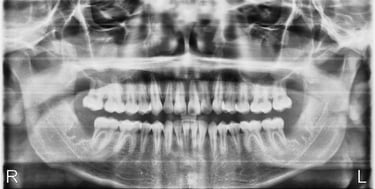

After